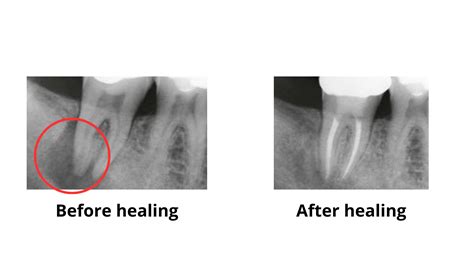

The progression from minor decay to a full-blown teeth root canal infection usually occurs in stages. Initially, bacteria enter the tooth's interior through a compromised enamel layer. Once inside the pulp chamber, these bacteria multiply, causing inflammation. As the pulp dies, toxins can escape through the tip of the tooth root and enter the surrounding bone, potentially forming an abscess.

1. Diagnosis: Digital X-rays are taken to visualize the infection.

Abscess Formation Severe pain; swelling; bone damage. High (Emergency Intervention)